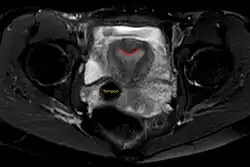

Arcuate uterus (marked in red) seen on MRI

The arcuate uterus is a form of a uterine anomaly or variation where the uterine cavity displays a concave contour towards the fundus. Normally the uterine cavity is straight or convex towards the fundus on anterior-posterior imaging, but in the arcuate uterus the myometrium of the fundus dips into the cavity and may form a small septation. The distinction between an arcuate uterus and a septate uterus is not standardized.